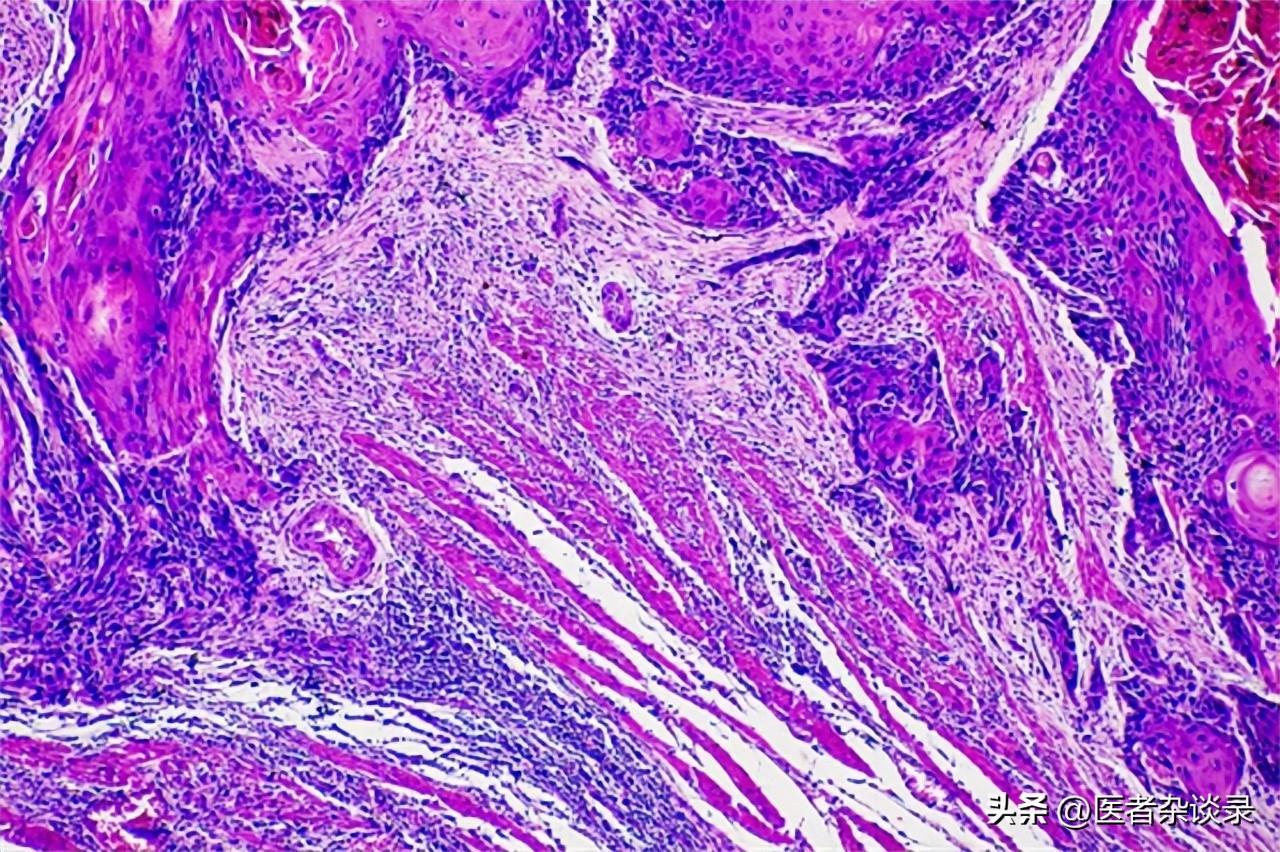

赵先生进行了口腔活检,发现活检组织中存在癌症细胞。

长期咀嚼槟榔后,槟榔中的槟榔碱、多酚和亚硝胺等物质可能会破坏口腔内部的微生态平衡,使发生氧化应激反应,损伤细胞从而激发炎性因子,促使上皮细胞在短时间内凋亡,同时还会阻止机体清除细胞外基质的蛋白质,导致蛋白沉积,进而造成口腔黏膜下纤维化(OSF)。患有OSF的患者通常会有口腔上皮萎缩、黏膜逐渐变硬、溃疡、张口受限等问题,且有可能会发展形成口腔癌。

另外,人们在食用槟榔时,口腔和胃部的细菌会产生一氧化氮,在一氧化氮环境下,这些生物碱会进行亚硝化反应,产生大量亚硝胺代谢物,增加细胞毒性和基因毒性;而亚硝胺与细胞其他分子相互作用后可能会加速口腔癌前病变,从而导致癌症的发生。